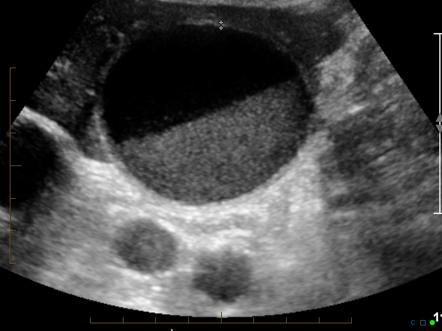

The gallbladder is located between the intestines and the liver. It stores bile from the liver until it’s time to release it into the intestines to aid in digestion. If the gallbladder doesn’t empty completely, particles in the bile, like cholesterol or calcium salts, can thicken from staying in the gallbladder for too long. They eventually become biliary sludge, which is commonly referred to as gallbladder sludge.